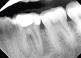

Case 1: 46 years old Male patient, ASA 1, presented for the evaluation and the treatment of tooth #36. On clinical examination the tooth was sensitive to percussion and palpation. The radiographic examination showed a very large radiolucency on both mesial and distal roots, a separated instrument in the mesio-lingual canal. The diagnosis of previously initiated with symptomatic apical periodontitis was made, and the endodontic treatment was indicated.

Following aesthesia and rubber dam placement, access was performed, and canals were located. The coreonal fragment was removed and the apical fragment was bypassed. The canals were instrumented using Edge endo X7 files (EdgeEndo) to size 35.04 in the mesial canals and 40.04 in the distal canal.

Canals were obturated using hydraulic condensation using EdgeBioCeramic Sealer (EdgeEndo). Bioceramic cement was used for its antibacterial and bioactive properties. The one year follow up shows a complete healing of the lesion.

Fig. 1 The X-ray initially reveals the following findings: caries on the distal sur-face of tooth #24, mesial caries on tooth #25, and a root remnant associated with tooth #26.